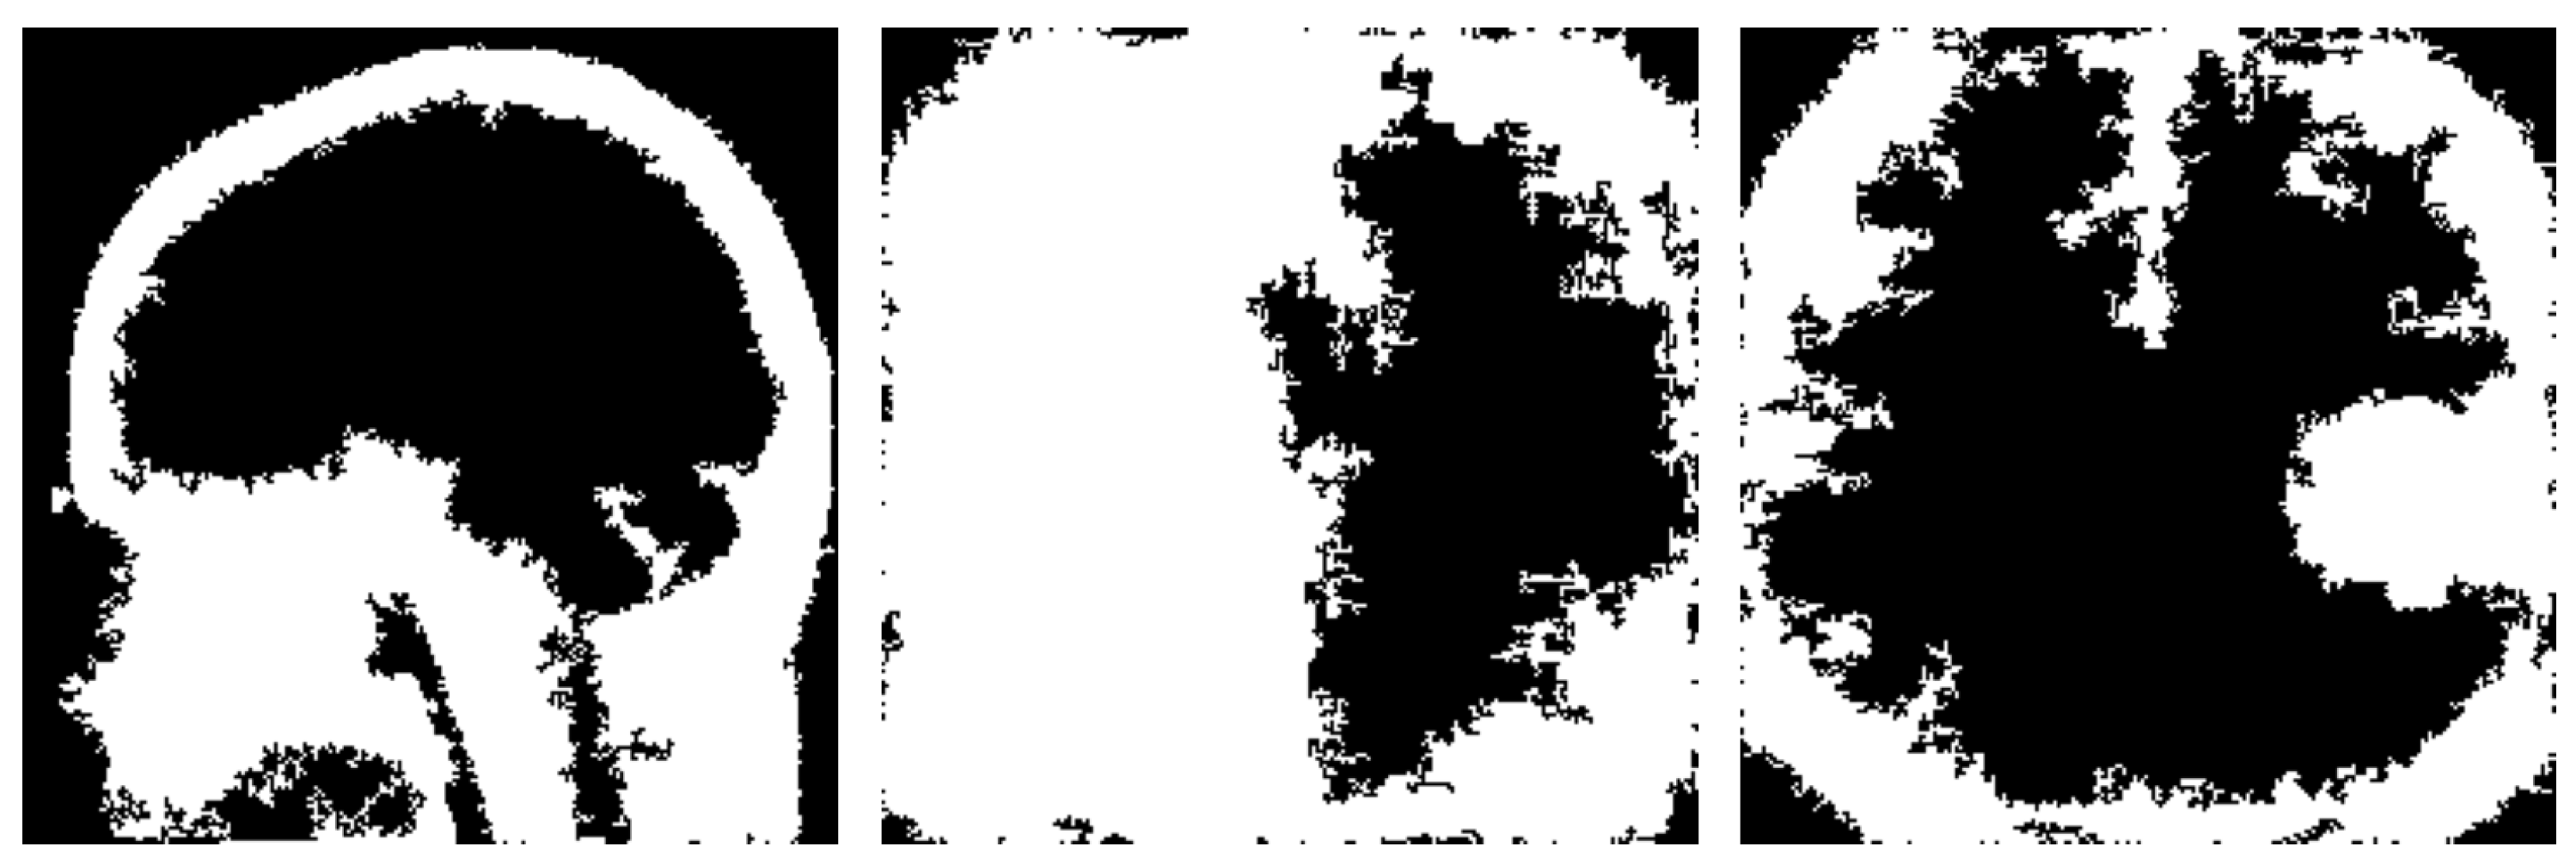

The result of an image after applying the Laplacian filter can be seen in Figure 3.

Finally, the gradient magnitude M ( x , y ) for each pixel is computed using the intensities of the image M ( x , y ) , where M ( x , y ) = ( I h o r ( x , y ) ) 2 + ( I v e r ( x , y ) ) 2 , and thresholding is then applied to the gradient magnitude in order to highlight edges. An example of vertical and horizontal sobel filters can be seen below in Figure 4.

Figure 3. Edge Detection example using Laplacian Filter.

Jimaging 10 00232 g003

Figure 4. Edge detection example using sobel filters.